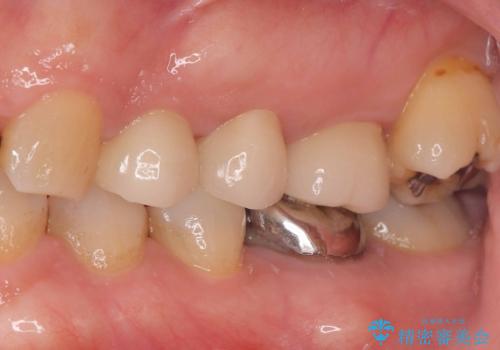

- 歯に穴が開くような虫歯があり銀歯の適合も悪く虫歯になっていたので、虫歯を除去後オールセラミッククラウンで治療を行いました。

左上5、6番の間に隙間もあったのでオールセラミッククラウンで隙間も閉じました。

歯に穴が開くような虫歯があり、銀歯と歯の堺に隙間があり(適合が悪い)そこが虫歯になっていたので適合良く(歯と被せ物の間に隙間が無い)作れるオールセラミッククラウンで治療を行いました。